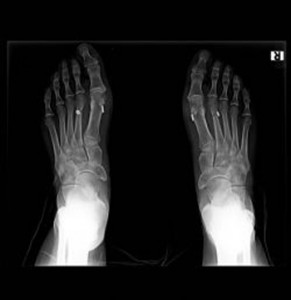

Olgu örneği: